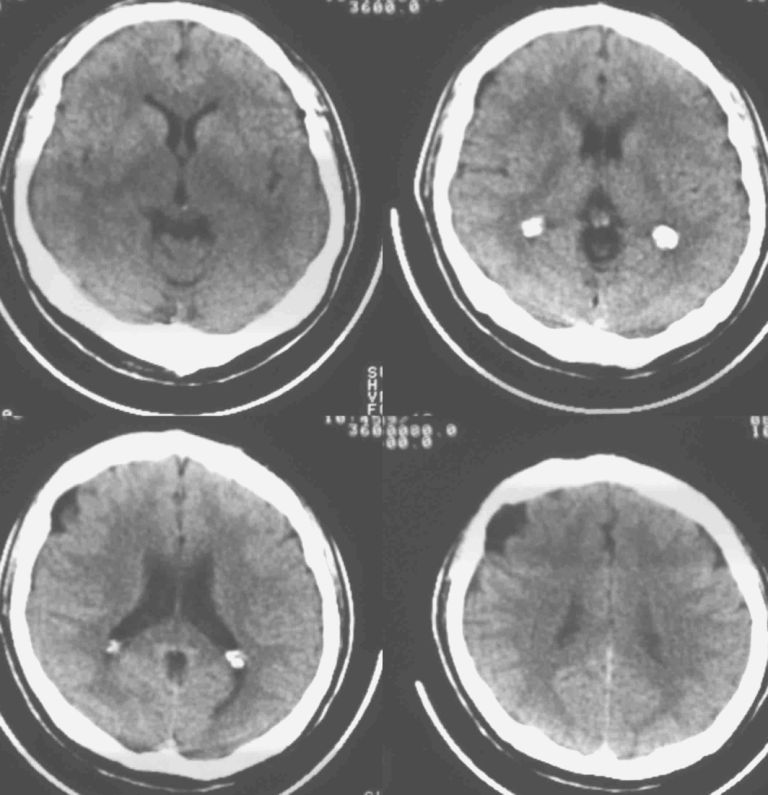

男37岁头持续性痛1天。右额部蛛网膜下腔囊肿诊断是否正确,请老师们帮忙看看。谢谢!

支持右额区蛛网膜囊肿。

有顶叶蛛网膜下腔囊肿

右侧额叶蛛网膜囊肿。